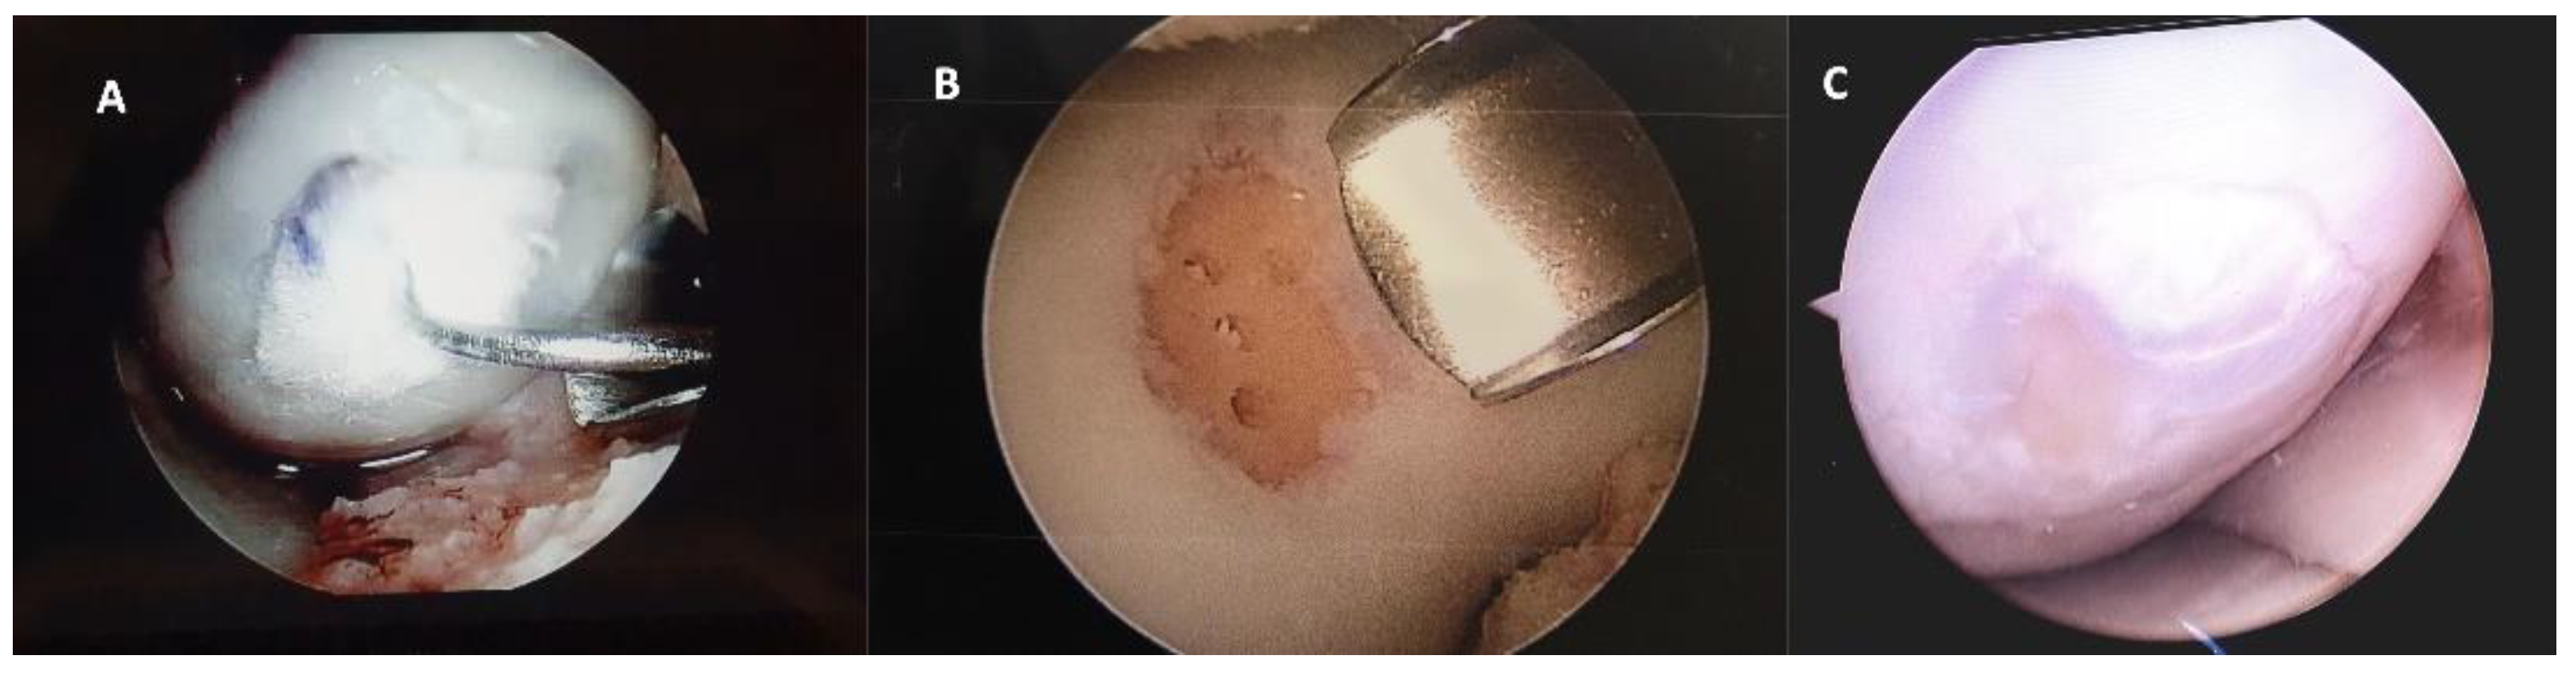

Figure 4. Representative macroscopic view of the cartilaginous repair tissue within the circular full-thickness cartilage defects and adjacent cartilage during surgery for A HA 3-D scaffold and B microfractures group. Letter C is the macroscopic view of the second look arthroscopy (12 months) for the patient treated with HA 3-D scaffold with the graft completely integrated to the normal adjacent articular surface, without evident filling defects.

After 12 months of follow-up a small number of patients required a new arthroscopy, during this second look the integrity of the graft was verified to assess the degree of defect, fill, graft integration to adjacent normal articular surface, and gross appearance of the graft surface, we were unable to observe a case without integration to adjacent normal articular tissue (Figure 4).